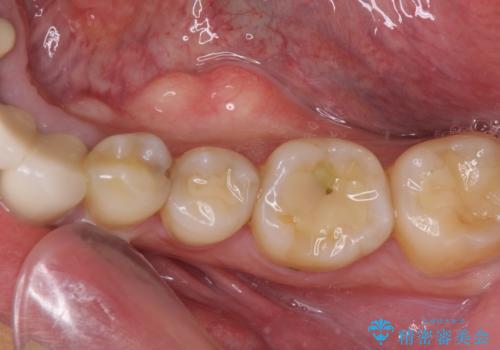

目立つ銀歯を治したい 奥歯のむし歯治療